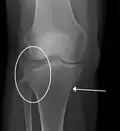

Una fractura de meseta tibial vista con rayos-X

La causa suele ser un trauma, como una caída o una colisión de un vehículo de motor. Los factores de riesgo incluyen osteoporosis y ciertos deportes como el esquí. El diagnóstico generalmente se sospecha en función de los síntomas y se confirma con rayos X y una tomografía computarizada. Es posible que algunas fracturas no se vean en las radiografías simples.

En todas las lesiones a la meseta tibial es imperativo efectuar radiografías (generalmente llamados rayos X). Las tomografías computarizadas no son siempre necesarias pero algunas veces son indispensables para evaluar el grado de fractura y determinar un plan de tratamiento que no sería posible con simples radiografías. Las imágenes de resonancia magnética son la modalidad de diagnóstico preferidas cuando se sospechan fracturas de menisco, ligamentos y/o tejidos. La angiografía-TC debe ser considerada si existe una alteración de los pulsos distales o cuando exista preocupación de una lesión arterial.